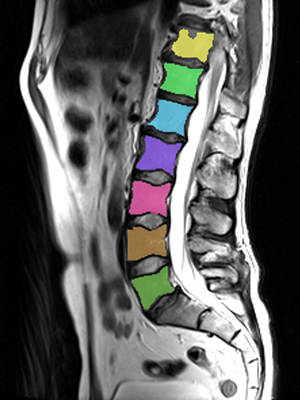

We trained and evaluated the method with five sets of CT and MR scans that visualize the spine. Reference segmentation masks for four of these datasets are publicly available, which allowed for a comparison with other publications that used the same data. Examples of images from the datasets are shown in Figure 3.

Similar performance was achieved for vertebra segmentation in various CT datasets with an average Dice score of and for vertebral body segmentation in an MR dataset with an average Dice score of . Surface distances were lower on CT images compared to MR images ( vs. ), however, there were also fewer training scans available in the MR dataset. Figure 4 illustrates the magnitude of differences of the automatic segmentations from the ground truth segmentations.

(a) Low-dose chest CT

(b) Lumbar spine CT (xVertSeg.v1 dataset)

(c) Lumbar spine MR

In the CT datasets, the segmentation was more accurate on high-resolution dedicated spine scans of healthy subjects compared with low-dose low-resolution chest CT scans and scans of subjects with in some cases severe compression fractures. This is also visible in the segmentation performance stratified by vertebra (Figure 5). Segmentations were more accurate for the lumbar (L1-L5) than for the thoracic vertebrae (T1-T12), which are covered by the more challenging low-dose chest CT scans. Outliers among the lumbar vertebrae correspond to vertebrae from the xVertSeg.v1 dataset, which features a number of severely deformed lumbar vertebrae that are particularly challenging to segment.